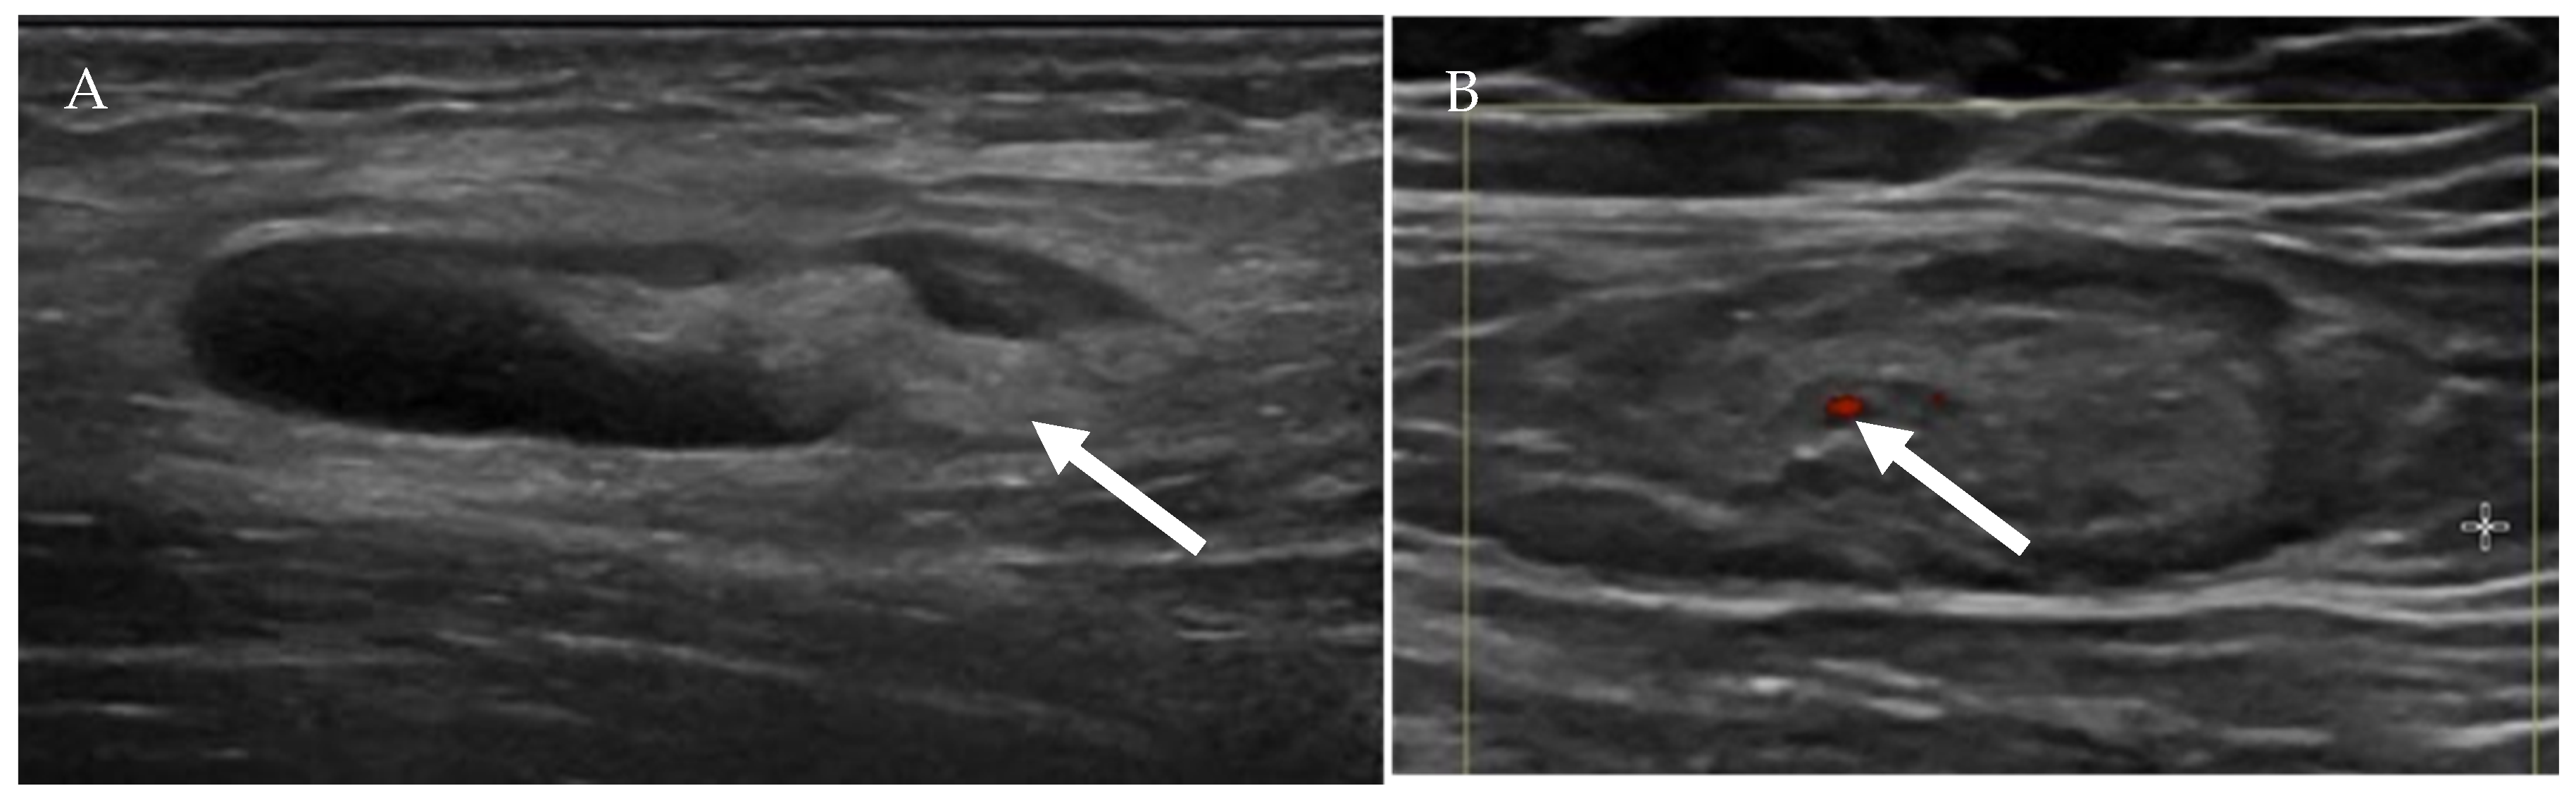

4.1.1. Ultrasound Evaluation of the Lymphatic System

- Prativadi, R.; Dahiya, N.; Kamaya, A.; Bhatt, S. Chapter 5 Ultrasound Characteristics of Benign vs Malignant Cervical Lymph Nodes. Semin. Ultrasound CT MRI 2017, 38, 506–515. [Google Scholar] [CrossRef]

- Dudea, S.M.; Lenghel, M.; Botar-Jid, C.; Vasilescu, D.; Duma, M. Ultrasonography of superficial lymph nodes: Benign vs. malignant. Med. Ultrason. 2012, 14, 294–306. [Google Scholar]

| US Criteria | Benign Lymph Node | Malignant Lymph Node |

|---|---|---|

| Size | <1 cm in short axis | ≥1 cm in short axis |

| Shape | Oval or elliptical | Round |

| Border | Indistinct | Sharp |

| Echogenicity | Hypoechoic | Very hypoechoic |

| Hilum | Maintained fatty hilum | Absent fatty hilum |

| Vascularity | Avascular or hilar vascularity | Peripheral or mixed |

| Resistive index | Low | High |